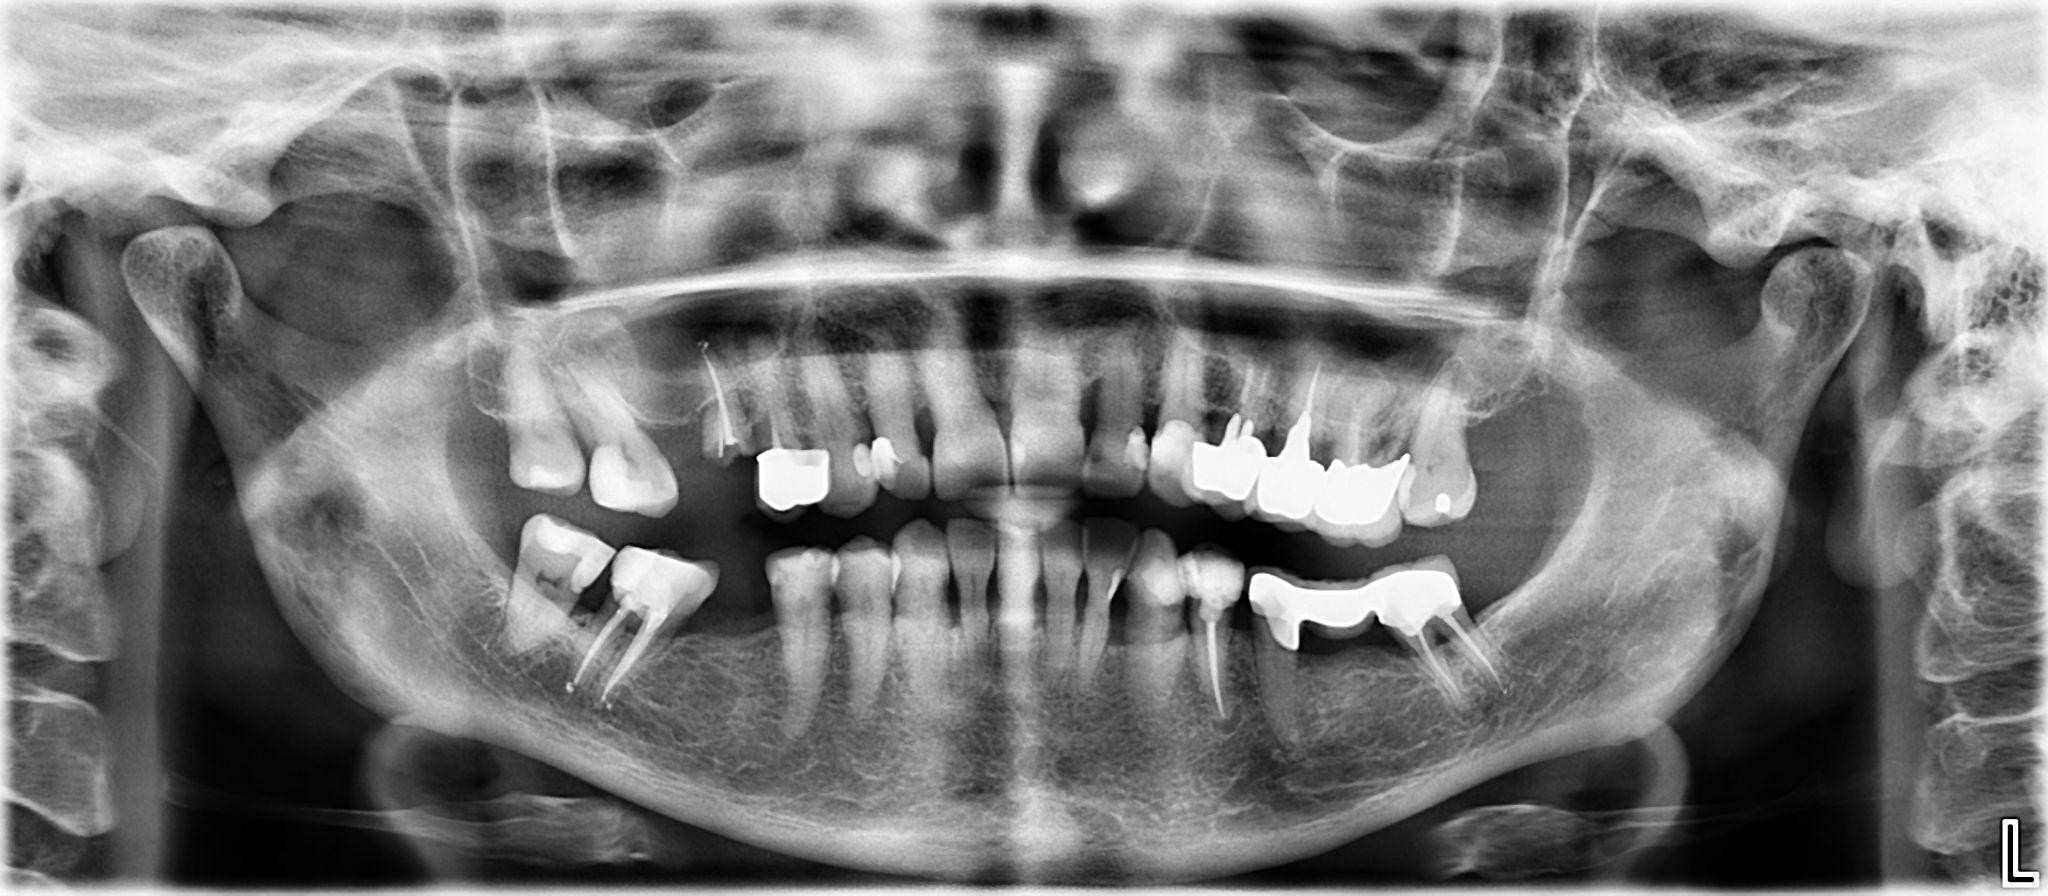

8. What option cannot be selected for the upper jaw of this panoramic X ray?

9 / 25

9. What option cannot be selected for the lower jaw of this panoramic X ray?

10 / 25

10. What option cannot be selected for the first quadrant of this panoramic X ray?

11 / 25

11. What option cannot be selected for the second quadrant of this panoramic X ray?

12 / 25

12. What option cannot be selected for the third quadrant of this panoramic X ray?

13 / 25

13. What option cannot be selected for the forth quadrant of this panoramic X ray?